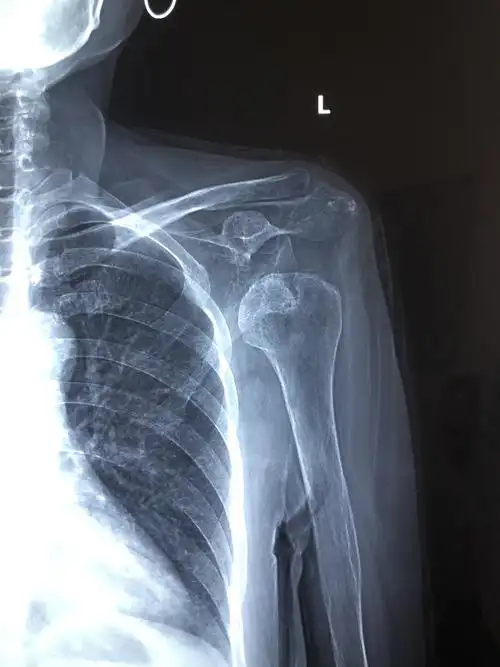

请问左肩锁关节脱位需要手术吗

肩锁关节脱位